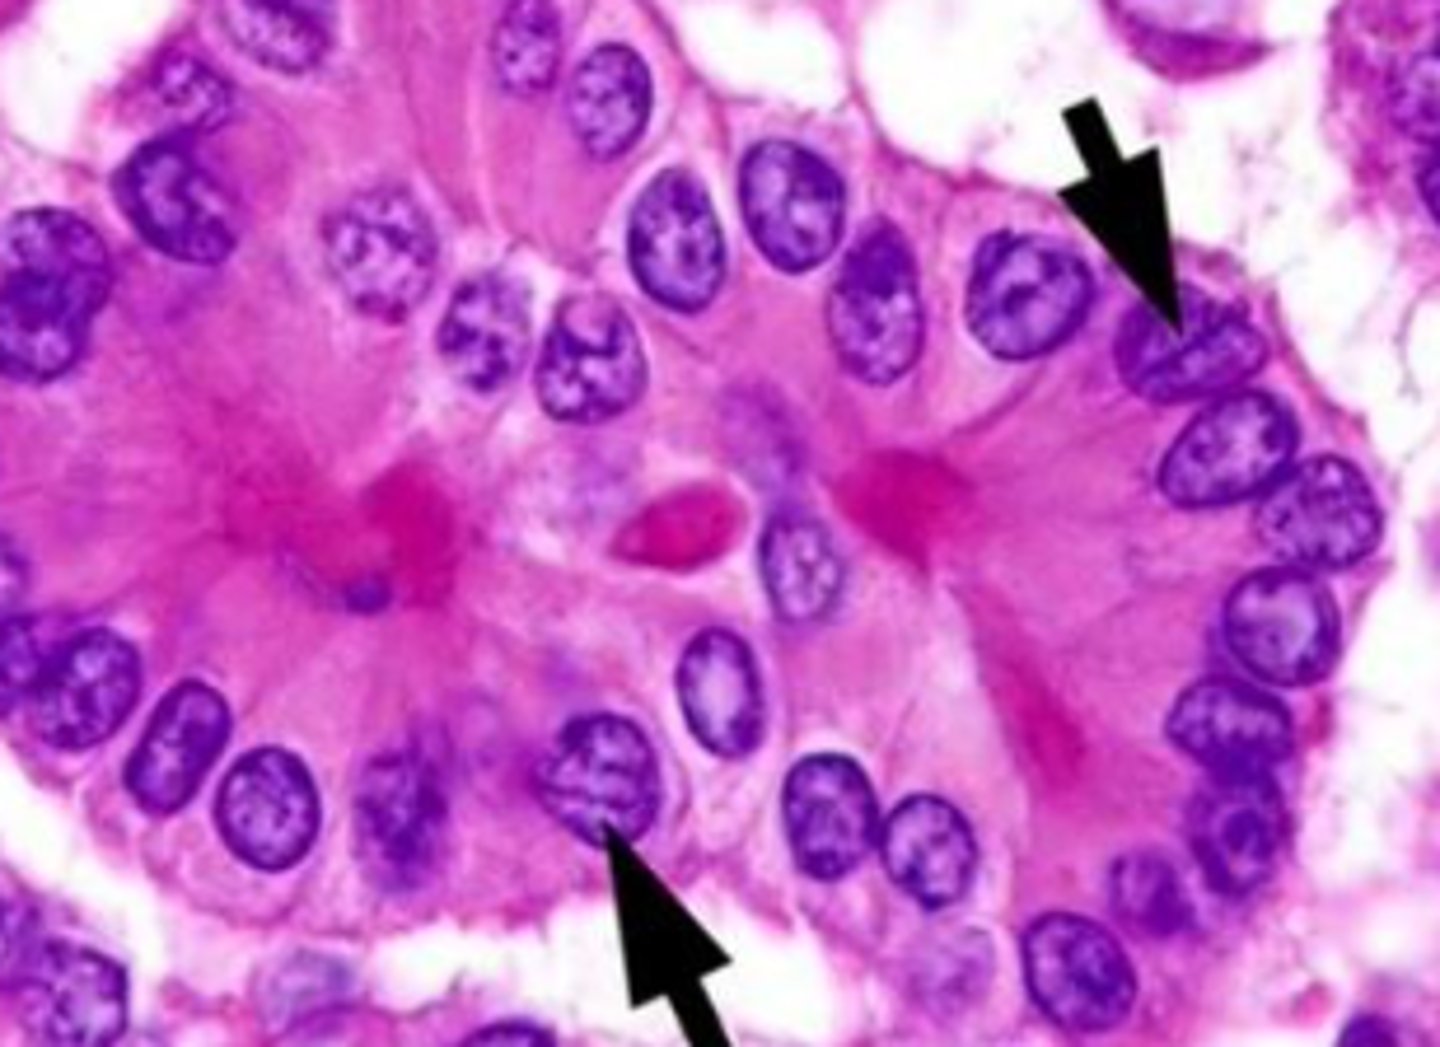

-clear/empty appearance---> ground glass or orphan annie eye nuclei

nuclear morphology of pappillary carcinoma

orphan annie eye nuclei

Seen in Papillary Carcinoma of the Thyroid. Enlarged thyroid cells with ground glass nuclei

intranuclear "pseudo-inclusion"

intranuclear grooves of papilllary carcinoma

Psammoma bodies

calcified struuctures in papilllary carcinoma

-indicates lymphatic invasion